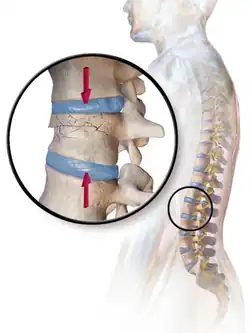

- Compression fracture/wedge fracture – usually occurs in the vertebrae, for example when the front portion of a vertebra in the spine collapses due to osteoporosis (a medical condition which causes bones to become brittle and susceptible to fracture, with or without trauma)

- Compression fracture – a collapse of a vertebra, often in the form of wedge fractures due to larger compression anteriorly

| Photo | Type | Description | Causes | Effects |

|---|---|---|---|---|

![]() |

Compression fracture/wedge fracture | Usually occurs in the vertebrae, for example, when the front portion of a vertebra in the spine collapses due to osteoporosis (a medical condition which causes bones to become brittle and susceptible to fracture, with or without trauma) | ||